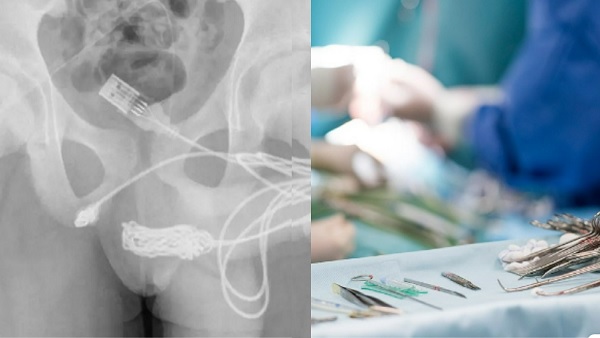

नई दिल्ली, 07 सितंबर: एक बेहद ही अजीबो-गरीब मामला सामने आया है। इसपर विश्वास करना थोड़ी मुश्किल हो सकती है, पर सत्य है। एक किशोर अपने प्राइवेट पार्ट के अंदरूनी हिस्सों को यूएसबी केबल से मापने की कोशिश कर रहा था। इस बीच उसके लिंग में यूएसबी केबल फंस गया। इससे उसे काफी परेशानी होनी लगी। जब उसे अस्पताल पहुंचाया गया तो डॉक्टर भी हैरान हो गए।

बता दें कि इस बच्चे ने प्रयोग के दौरान अपने प्राइवेट को नाप रहा था। इसी बीच उसके अंदर केबल फंस गया। निजी अंगों के अंदरूनी हिस्सों को मापने का प्रयास करने के दौरान वह फंस गया और केबल में गांठों और उलझनों के कारण लड़के के पेशाब में खून आने लगा।

साइंस डायरेक्ट की रिपोर्ट में डॉक्टरों ने लिखा कि यूएसबी वायर के दो डिस्टल पोर्ट बाहरी यूरेथ्रल मीटस से बाहर निकलते हुए पाए गए, जबकि नॉटेड वायर का मध्य भाग यूरिनल के भीतर फंसा रहा।

चिकित्सकों ने कहा कि तार के दोनों सिरों को बाहरी मूत्रमार्ग के माध्यम से सफलतापूर्वक बाहर निकाला गया। लड़का ठीक हो गया और उसे छुट्टी दे दी गई। चेतावनी दी कि मूत्रमार्ग में वस्तुओं को डालने से पेशाब करते समय दर्द हो सकता है।